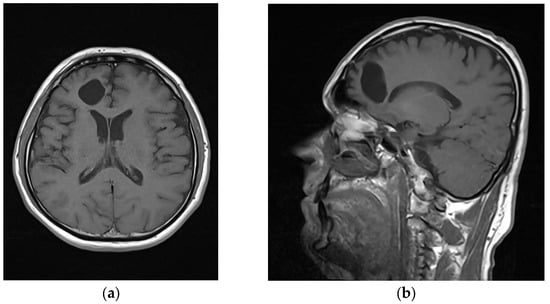

Following the closure of the wound, which involved the placement of an epicranial drain to facilitate drainage and prevent fluid accumulation, the patient underwent monitoring in the intensive care unit. Microbiological analysis of the purulent contents obtained from the abscess did not reveal the presence of any specific bacterial pathogens. The patient’s treatment plan included a 5-week course of intravenous meropenem. After the removal of the epicranial drain and a thorough neurological examination, which yielded normal findings, the patient’s condition demonstrated significant improvement. Consequently, the patient’s condition was deemed stable and appropriate for discharge from the hospital. A postoperative MRI scan was conducted to evaluate the structural changes in the patient’s brain. The MRI images clearly revealed the presence of a well-defined cavity at the surgical site, indicating the successful removal of the abscess (Figure 3a,b). Significantly, no pathological features or abnormalities were observed in the surrounding cerebral tissue. To ensure comprehensive postoperative care and monitor the patient’s neurological status, regular follow-up examinations were scheduled at 6-month intervals, with assessments conducted by both a neurologist and a neurosurgeon. These evaluations consistently demonstrated the absence of pathological sequelae or adverse outcomes.

Figure 3.

Postoperative MRI; (a) axial T2 slice; (b) sagittal T2 slice.